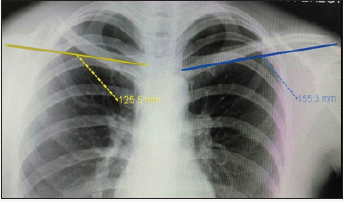

Upon pushing both palms against the wall with the elbows extended, the deformity disappeared. Specific assessment of the serratus anterior, trapezius and rhomboid muscles were normal. Nerve conduction study of the long thoracic and spinal accessory nerves was also normal. Radiographs revealed a displaced comminute clavicle shaft fracture with a shortening of 3cm (Figure 2). The clavicle fracture was treated surgically with open reduction and internal fixation using a distal clavicle locking compression plate (Synthes®) and augmented with autologous cortico-cancellous iliac crest bone graft (Figure 3). There was near complete resolution of the scapular winging upon inspection on the second day after surgery (Figure 4). The patient was also prescribed physiotherapy with emphasis on serratus anterior, rhomboid and trapezius muscle strengthening. On the first follow up after 2 weeks of surgery, complete resolution of winging. During second follow up after 2 months of post-operative, she had good shoulder range of motion.

Figure 2: Chest radiograph showing right clavicle midshaft fracture with 3cm shortening.